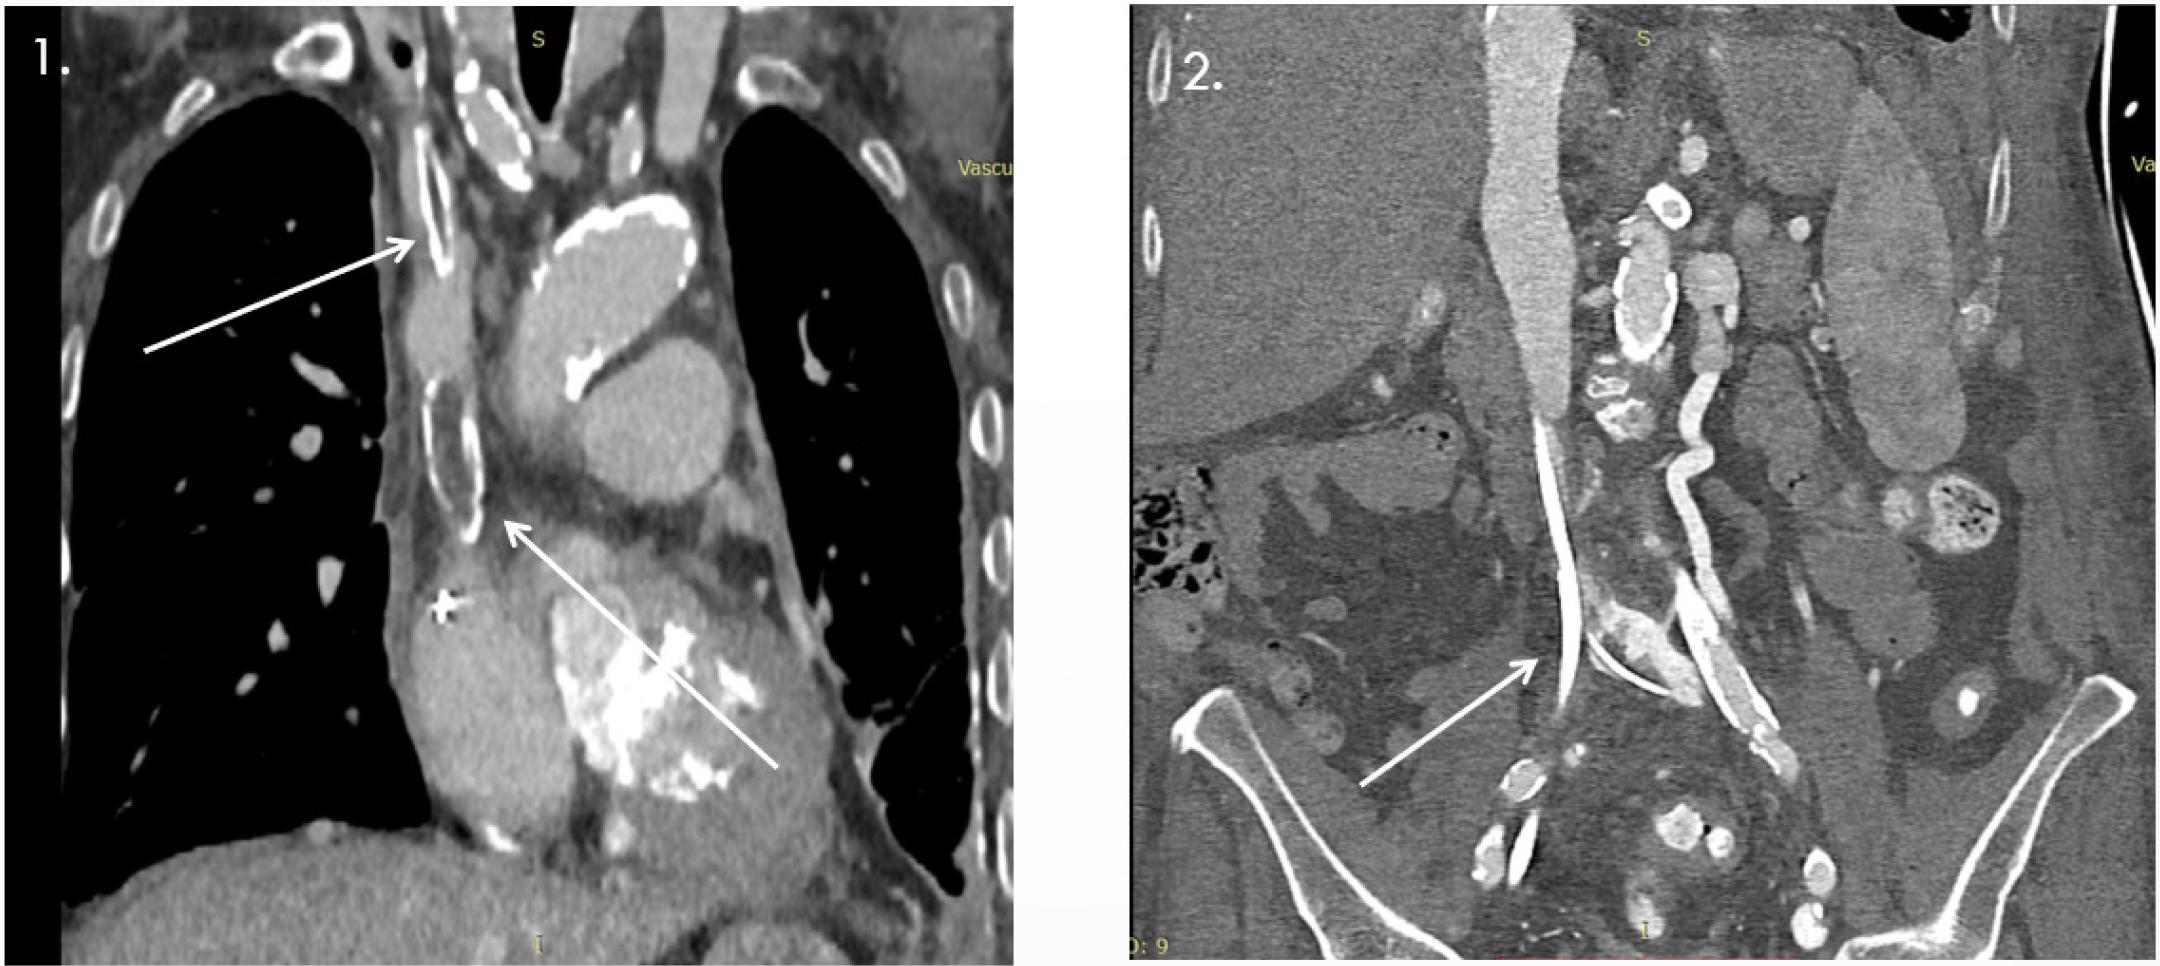

A thoracic CT scan confirmed the temporary pacemaker lead at the right ventricular apex. It also showed extensive mitral annular calcification extending to the mitral-aortic continuity and aortic root, with two small cavitary defects (up to 30 mm), as well as vascular calcifications involving the aorta, supra-aortic trunks, and proximal coronary arteries (Summary Figure 3). Additional findings included distal SVC occlusion by a ~4 cm thrombus with a hyperdense peripheral component, likely a fractured catheter fragment. Another catheter fragment (35 × 6 mm) was identified in the left brachiocephalic vein with a thrombosed lumen and partial obstruction. Extensive thoraco-abdominal collateral venous circulation was noted. The left subclavian, brachiocephalic, jugular veins, and IVC were patent, though the proximal and mid-left subclavian vein showed stenosis, likely residual thrombus (Summary Figure 4).

1- Oclussion VCS due to ‘forgotten* dialysis catheter; 2 - Stenosis and oclussion of inferior vena cava and collateral circulation between the left common iliac vein and the left renal vein.

3- Important collateral circulation thoraco-abdominal; 4- Important collateral circulation thoraco-abdominal.

Contrast-enhanced CT via the right antecubital vein revealed severe proximal IVC stenosis (~9 mm length, residual lumen 1–2 mm, 2.5 cm above iliac confluence) with partially calcified thrombus, extensive collateral venous circulation, ruptured calcified catheter fragments, and a right iliac venous stent. The left common iliac vein was ligated with collateral flow; the left renal vein was dilated. The aorta showed diffuse calcification and stenosis, with focal ectasia and thrombus at the IMA origin raising suspicion of a small aorto-duodenal fistula. Significant stenoses were also noted at the SMA and celiac origins, with heavily calcified iliac arteries (Summary Figures 5).